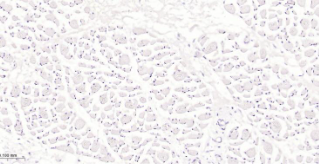

Immunohistochemical analysis of paraffin embedded human skeletal muscle tissue slide using IHC0497H (Human CBS IHC Kit).